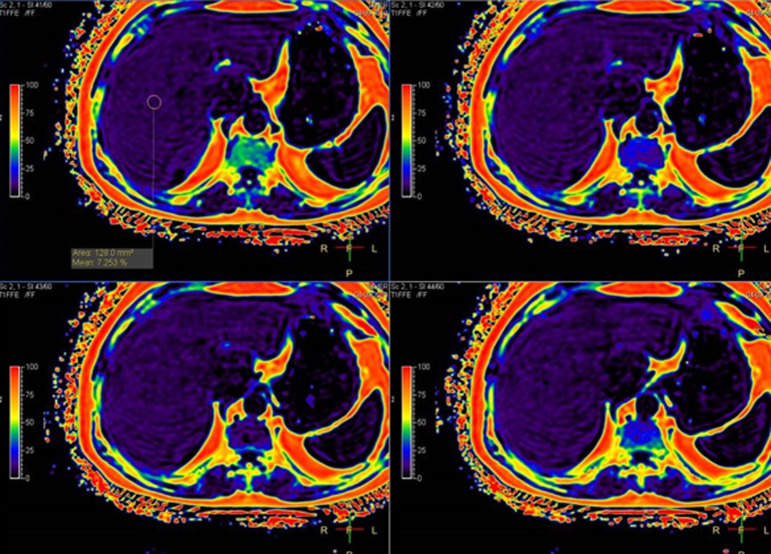

Material and methods: This study comprised 48 stable chronic obstructive pulmonary disease patients who were diagnosed and categorized using the Global Initiative for Chronic Obstructive Lung Disease 2017 criteria. The prevalence of nonalcoholic fatty liver disease in chronic obstructive pulmonary disease patients was determined using noninvasive biomarkers and imaging methods. Steatosis was detected using magnetic resonance mDIXON-Quant sequence imaging, while fibrosis was detected using the acoustic radiation force impulse and FIB-4 index.

Results: A total of 58.3% of the patients investigated had a fat level of 5%, and nearly a quarter of them had a fat content of 10% or more, and 45.8% of the patients studied had severe hepatic fibrosis. The Fibrosis-4 (FIB-4) index revealed advanced fibrosis in 18.75% of them. No statistically significant association was found between chronic obstructive pulmonary disease groups of studied patients and the presence of steatosis and fibrosis (≥F2) using acoustic radiation force impulse. The presence of fibrosis, however, was statistically significant linked with chronic obstructive pulmonary disease groups of examined patients using the FIB-4 index. γ-Glutamyl transferase and alkaline phosphatase levels were greater in Global Initiative for Chronic Obstructive Lung Disease 3/4 and C/D groups.